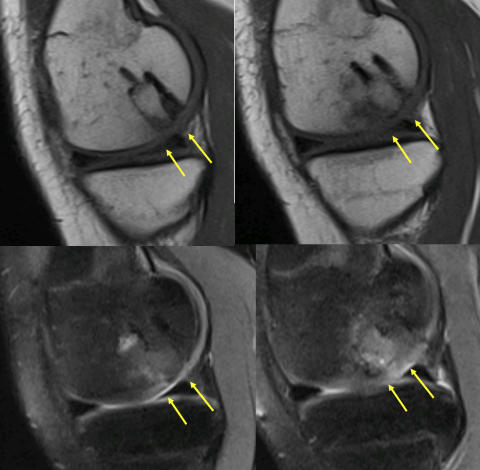

Ergenlik öncesinde saptanan ve altındaki canlı kemik yatağından ayrılmamış olan osteokondritis dissekans, çocukların yarısından fazlasında ameliyatsız iyileşebilir. Bunun için sportif aktivite kısıtlanır ve 6 aylık aralarla MRG takibi yapılır. Üzerindeki kıkırdağın bütünlüğü bozulmamış ve MR’larda ayrılma bulgusu yoksa, ölü kemik vücut tarafından onarılarak 2 yıl içinde iyileşme sağlanabilir (Resim 3). Bu takip için kaliteli bir MR görüntülemesi şarttır. MRG’lerde ayrılma bulgusu saptanan çocuklarda cerrahi tedavi gerekli olur. Her iki dizde osteokondritis varsa, seyirleri aynı olmayabilir. Bir taraf iyileşirken diğer taraf ayrılıp ameliyat gerektirebilir.

Resim 3 a,b: Ergenlik öncesi osteokondritis dissekans saptanan bir hastada ameliyatsız iyileşme. a: İlk başvuru anındaki MR görüntüleri; b: İki yıl sonra kıkırdak ayrılması olmadan iyileşme tamamlanmış.